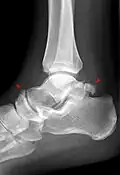

Ankle

Accessory bones at the ankle mainly include:

- Os subtibiale, with a prevalence of approximately 1%.[14] It is a secondary ossification center of the distal tibia that appears during the first year of life, and which in most people fuses with the shaft at approximately 15 years in females and approximately 17 years in males.[14]

- Os subfibulare, with a prevalence of approximately 0.2%.[15]

Os trigonum (further described below) may also be seen on an ankle X-ray.